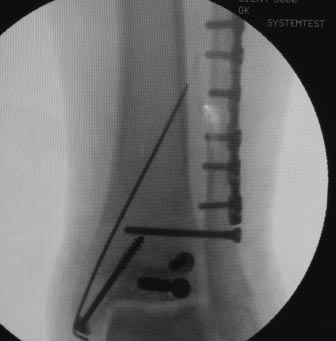

Уважаемые коллеги, всем огромное спасибо за рекомендации. Сегодня

прооперировали. Презервативы в операционной оказались кстати :)

Фото синтеза прилагаю. Качество не ахти, так как фоткал с экрана. Но все

видно.